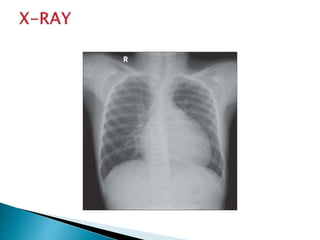

 Respiratory distress

 Tachypnea

 Asymmetric lung expansion.

 Decreased tactile fremitus

 Hyperresonance on percussion

 Distant or absent breath sounds

In many cases we need only observation and

serial CXR follow up daily , the air will be

absorbed.